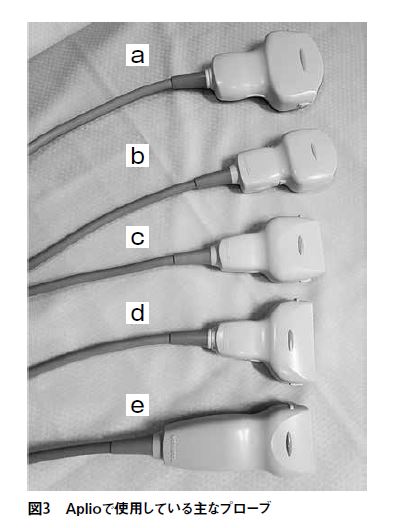

Aplio500で、私が常に使用しているプローブは、下記の5種

類である(図3)。

図3の上部から順に

1. コンベックスプローブ PVT-375BT(中心3.5MHz、視野角約70°)(図3-a)

主にスクリーニングの腹部検査に用いる。

2. 高周波コンベックスプローブ PVT-674BT(中心6.0MHz 視野角約65°)(図3-b)

胆嚢壁や総胆管、膵臓の微細な病変などを見たい時、また体厚のある被検者の消化管や、血管系(特に下肢深部静脈)に用いる。

3. リニアプローブ PLT-704SBT( 中心7.5MHz 視野幅約38mm)(図3-c)

血管系(頸動脈、下肢深部静脈)に用いる。

消化管検査、小児の腎臓、胆道系の描出にも用いる(図4)。

4. リニアプローブ PLT-1005BT(中心10.0MHz 視野幅約58mm)(図3-d)

乳腺、甲状腺など表在領域に用いる。

消化管検査(特に消化管の壁辺縁や周囲リンパ節の描出)などにも用いる(図5)。

5. リニアプローブ PLT-1204BX(中心12.0MHz 視野幅約38mm)(図3-e)

表在領域、末梢血管、リウマチ検査の手指関節描出に用いる。

上記のごとく5本のプローブを見たい領域、被検者の体格に合わせて使い分けている。プローブを変更したときにもクイックスキャンのボタンを押すだけで、患者の体型や検査目的に応じて、組織とノイズ信号を識別し、組織信号のみを最適化してモニタ上に適正な画像を提供してくれるのだ。